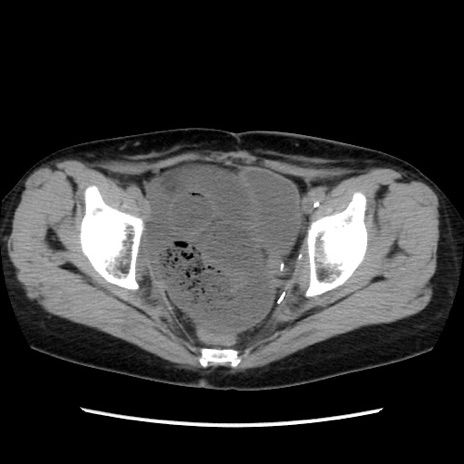

冠状断像

【症例】40歳代 女性

【主訴】上腹部痛、嘔気・嘔吐

【現病歴】約9時間前頃から急に上腹部痛、嘔気、嘔吐が出現。改善しないため救急要請。

【既往歴】子宮頚癌(広汎子宮全摘術、放射線療法)、腸閉塞

【身体所見】腹部:平坦、軟、腸雑音亢進、上腹部を中心に腹部全体に圧痛あり。

【データ】WBC 8400、CRP 0.03